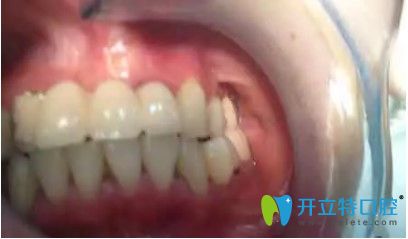

劉女士,33歲,據(jù)她描述,自己多年前在國內(nèi)一家口腔醫(yī)院做了烤瓷冠,但由于時(shí)間長變的松動(dòng),考慮到自己還年輕,為了一步到位,她來韓國安特麗做了多顆牙種植。

在拆除烤瓷橋后,發(fā)現(xiàn)她的口內(nèi)埋伏牙,把埋伏牙拔除后,很順利的植入了種植體,完成了種植牙。

劉女士反饋,自己很后悔當(dāng)初做了烤瓷牙,她表示,自己對(duì)韓國的種植牙技術(shù)很認(rèn)可,所以來韓國做了種牙手術(shù)。